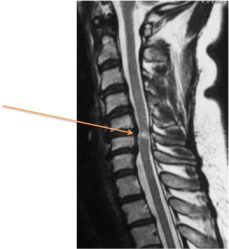

Une IRM permet d'évaluer l'état de la moelle épinière et notamment la présence d'un signal anormal en cas de myélopathie (Figure 3).

Figure 3. Compression lente de la moelle épinière cervicale se traduisant par un hypersignal de la moelle (en blanc).